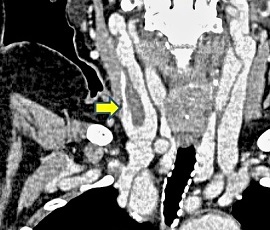

CT画像(矢印:血栓)